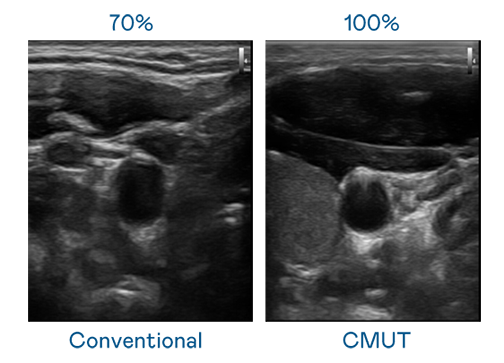

CMUT 技术是一种用电容式微机电元件来产生超音波讯号的技术。与传统 PZT 压电式技术相比,CMUT 频宽增加 30%,更宽频的超音波讯号让影像解析度大幅提升,是实现高影像品质医疗超音波扫描、促进精准医疗发展的关键技术。

超音波影像的解析度高低,首先取决于探头能发出的讯号频宽。BB视讯 CMUT 可提供高清晰的超音波讯号,提供高频宽、高灵敏度、影像纹理细节更高的超音波影像,协助医护人员缩短影像判读时间及利用精准的医疗影像进行诊断。